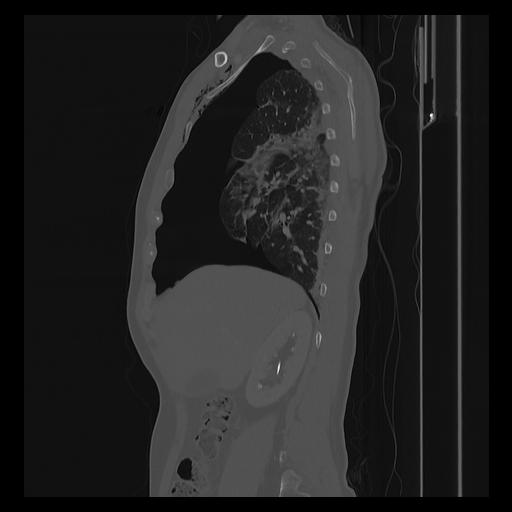

33 PULMON,CE,Sagittal,3.000,PULMON,Sagittal,